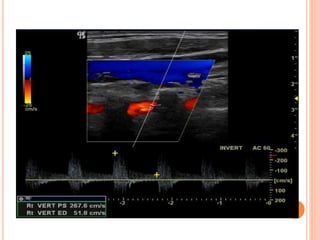

3- SUBCLAVIAN STEAL PHENOMENON

subclavian artery with retrograde flow in ipsilateral

vertebral artery

VERTEBRAL TO SUBCLAVIAN STEAL

Presteal

Incomplete steal

Complete steal

Compared to bunny in profile